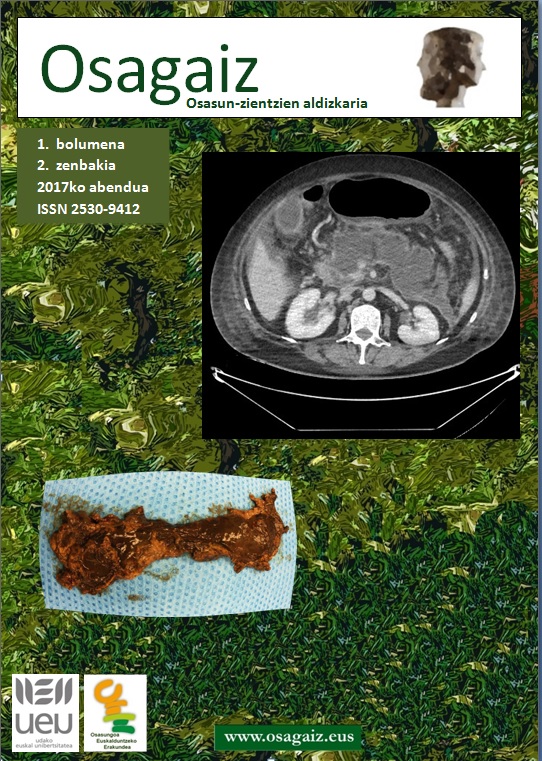

- Pankreatitis akutua duen pazientearen artatzea. Felix Zubia-Olaskoaga